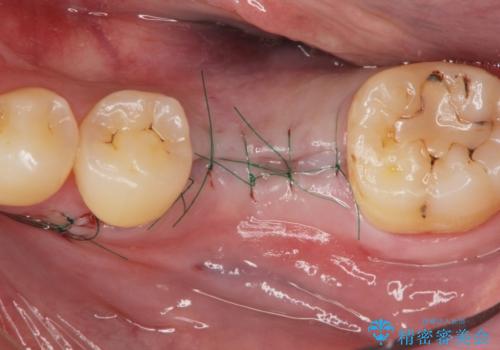

減ってしまった顎骨に増骨処置を行うことで、より安定した環境で長く使用できるようなインプラント治療を行っています。

- 外科手術のため、術後に痛みや腫れ、違和感を伴います

- メンテナンスを怠ったり喫煙により、お口の中に大きな悪影響を及ぼすインプラント周囲炎等にかかる可能性があります